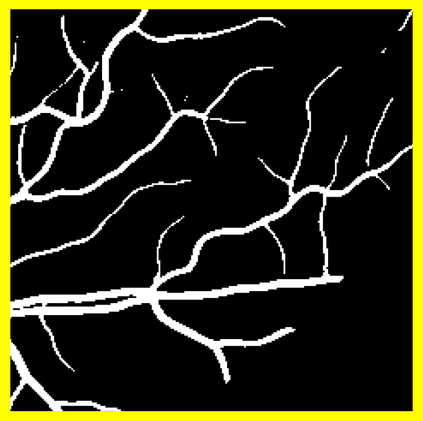

Blood vessel segmentation is crucial for many diagnostic and research applications. In recent years, CNN-based models have leaded to breakthroughs in the task of segmentation, however, such methods usually lose high-frequency information like object boundaries and subtle structures, which are vital to vessel segmentation. To tackle this issue, we propose Boundary Enhancement and Feature Denoising (BEFD) module to facilitate the network ability of extracting boundary information in semantic segmentation, which can be integrated into arbitrary encoder-decoder architecture in an end-to-end way. By introducing Sobel edge detector, the network is able to acquire additional edge prior, thus enhancing boundary in an unsupervised manner for medical image segmentation. In addition, we also utilize a denoising block to reduce the noise hidden in the low-level features. Experimental results on retinal vessel dataset and angiocarpy dataset demonstrate the superior performance of the new BEFD module.

翻译:近些年来,有线电视新闻网的模型导致分离任务突破,然而,这类方法通常会失去物体边界和对船只分割至关重要的微妙结构等高频信息;为解决这一问题,我们提议加强边界和地貌分解模块,以促进网络能力,在语义分解中提取边界信息,这种信息可以以端到端的方式纳入任意编码器-分解器结构。通过引入索贝尔边缘探测器,网络能够在之前获得更多边缘,从而以不受监督的方式加强医疗图像分解的边界。此外,我们还利用一个分解区块来减少低层特征中隐藏的噪音。关于再生容器数据集的实验结果和血管合成数据集显示了新的BEFD模块的优异性性表现。